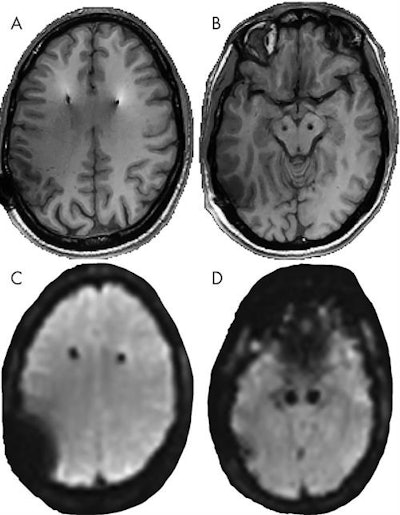

The researchers found no MRI-related short- or long-term adverse events or acute changes among the subjects. They observed artifacts most prominently near the electrode contacts and in the frontoparietal cortical area where extension wire is located.

Electrode contact artifacts had a mean diameter of 9.3 mm (± 1.6 mm), and 1.9% (± 0.8%) of the brain was obscured by a coil artifact. Coil artifacts were significantly larger on 3-tesla MRI, obscuring 2.1% (± 0.7%) of intracranial volume, compared with 1.4% (± 0.7%) obscurity on 1.5-tesla MRI (p < 0.001).

Even with the larger percentage of the brain obstructed by coil artifact at 3 tesla, the authors emphasized that "most of the brain is visible and fit for analyses such as functional MRI."